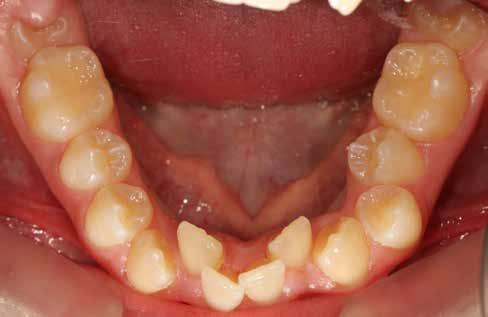

Ebben a cikkben egy 16 éves lánypáciens esetét szeretném bemutatni (1–7. képek)

A Pitts21-es fix készülékes kezelés során a harapásemelőket a felső nagyőrlő fogakra ragasztottuk, hogy a felső molárisok intrúziójával segítsék a harapás zárását (8. kép) Ún. keresztharapásos, majd később normál class 2-es gumihúzással (9–10. képek), továbbá az elülső fogakon alkalmazott ún. Rainbow harapás-záró gumihúzással (11. kép) korrigáltuk a jobb oldali teljes premolárisnyi distal-harapást, valamint az elülső nyitott harapást.

A fix fogszabályozó készülék mindössze 16 hónapos kezelés után került eltávolításra! Páciensünk legnagyobb örömére állcsontműtét nélkül sikerült mind az arcesztétikai, mind a funkcionális rehabilitáció (13–18. képek)

Minden fogszabályozó kezelés után nagyon fontos a retenció, de ilyen eltérés esetén különösen, mivel a recidíva veszély nyitott harapás esetén a legnagyobb. A fogak és a harapás megtartása fix és kivehető retainer-ekkel történik.

A kivehető helyben-tartók legfontosabb eleme a mindkét fogívet összekötő ún. Splint (19. kép), amely egyrészt saggitálisan tartja a helyén a mandibulát, hogy ne csússzon vissza hátrafelé, másrészt segít a harapás zártan tartásában a növekedés teljes befejeződéséig.